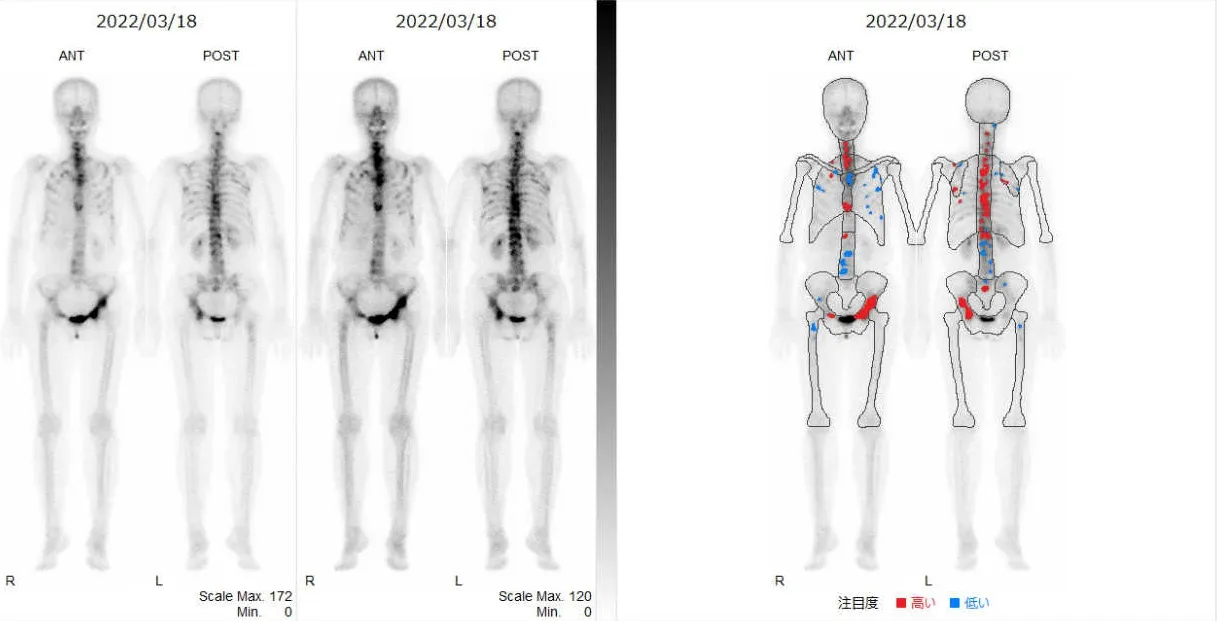

核医学検査は放射性同位元素を用いた画像検査です。がん診療においては転移箇所の検索に行われます。骨シンチグラフィ検査は、骨の代謝を画像化することができ、骨への転移を比較的早期に見つけることができます。

骨シンチグラフィの画像

骨シンチグラフィ(乳癌全身骨転移)